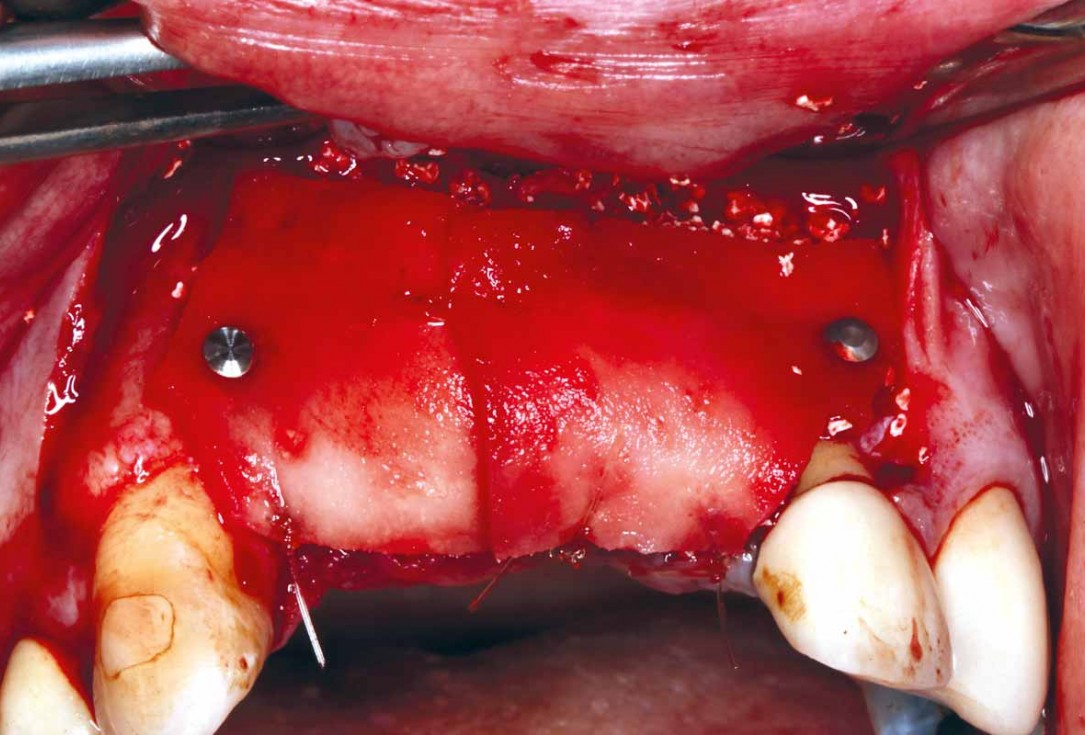

10/27 - mucoderm® was stabilised using titanium pins and sutured together to achieve maximum stability

GBR and soft tissue augmentation with cerabone® and mucoderm® - H. Maghaireh & V. Ivancheva